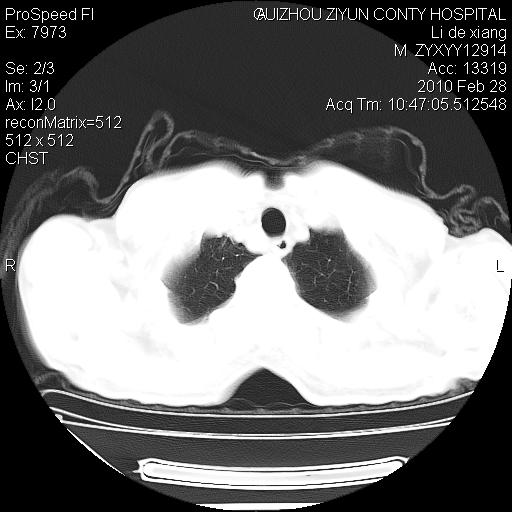

标题: CT24776:男 71Y 咳嗽咳痰胸痛两月,伴声音嘶哑。 [打印本页]

标题: CT24776:男 71Y 咳嗽咳痰胸痛两月,伴声音嘶哑。

左侧中央型肺癌伴左肺上叶阻塞性肺炎及节段性不张可能性大,建议纤支镜检查!

左侧中央型肺癌伴左肺上叶阻塞性肺炎及节段性不张可能性大,建议纤支镜检查!纵隔淋巴结转移.

左肺门部肿块,伴左上肺斑块影,周边模糊,支持左肺中央型肺癌伴节段性不张及阻塞性肺炎,结合支气管镜检查。

左上叶支气管狭窄,阻塞性病变,肺门肿块,纵隔及肺门淋巴结增大,中央性肺癌

左肺中央型肺癌并阻塞性改变、纵膈 淋巴结转移

左侧中央型肺癌伴左肺上叶阻塞性肺炎及纵隔淋巴结转移